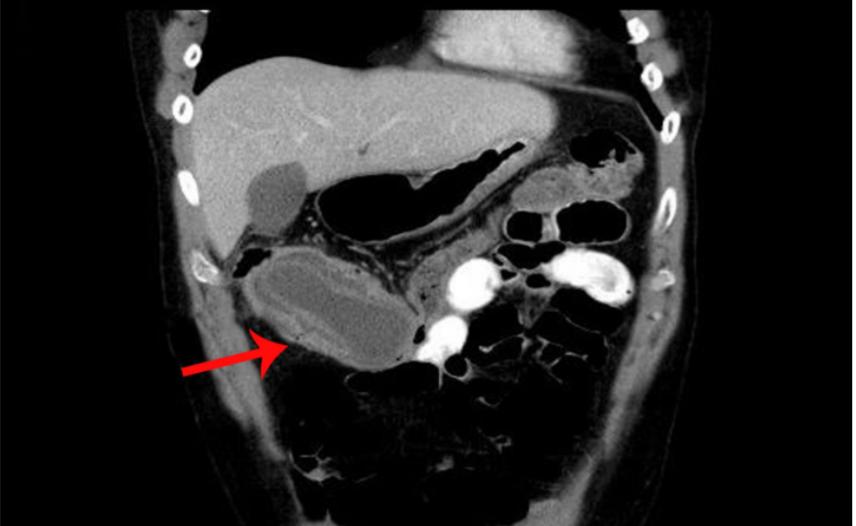

彩超和腹部CT对诊断肠套叠有较高的诊断率。肠套叠的腹部CT表现一般为软组织肿块影,常呈现"同心圆征"或"靶环征",有时称假肾征。有时肠管套入部较深,可表现为"双肠管征"。

双肠管征